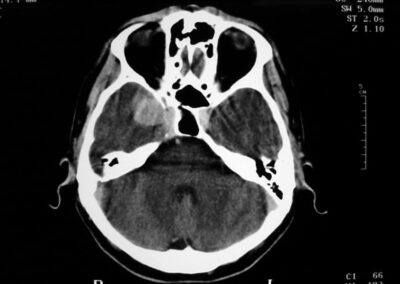

El diagnóstico se puede confirmar y el tumor localizar mediante:

• TAC cerebral

• RM cerebral